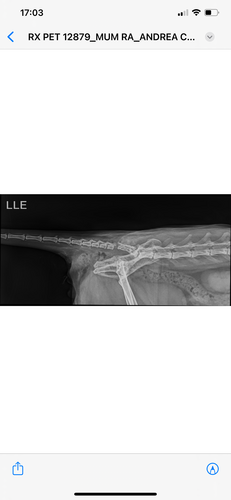

Este acidente ocasionou muitas lesões como: fratura de fêmur, deslocamento de bacia, fratura de cauda e perda de controle fisiológico.

Diante dessa situação, ele terá que passar por uma cirurgia de grande porte para estabilizar sua situação, nesta cirurgia ele colocará pinos na pata e removerá a cauda. Conseguimos um cartão de crédito para pagar as despesas mas está muito caro e precisamos de ajuda!